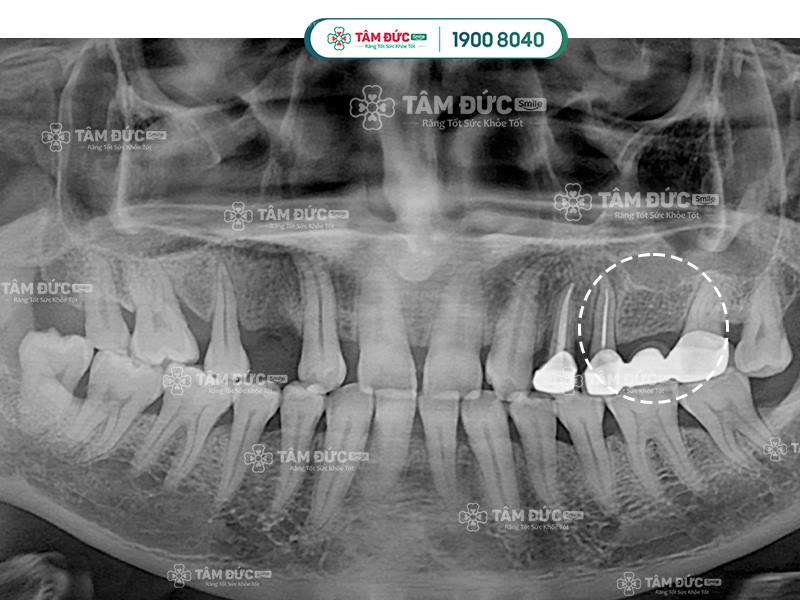

Cầu răng sứ không thể ngăn chặn tình trạng tiêu xương hàm khi mất răng

- Chân răng bên dưới vị trí mất răng sẽ tiêu biến dần vì không thường xuyên tác động khi ăn nhai

Phương pháp trồng răng Implant ngăn chặn tiêu xương hàm hiệu quả hơn làm cầu răng sứ